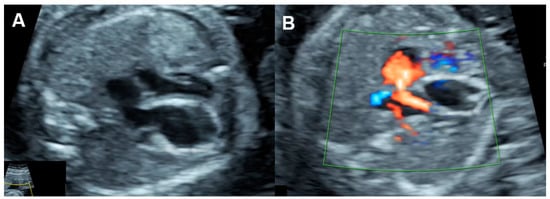

4.2. Fetal Cardiac Size

4.3. Fetal Valve Competency